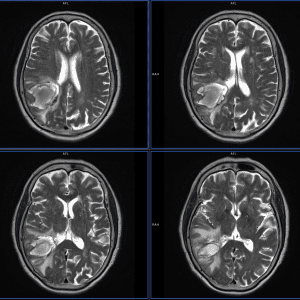

Kén sán não